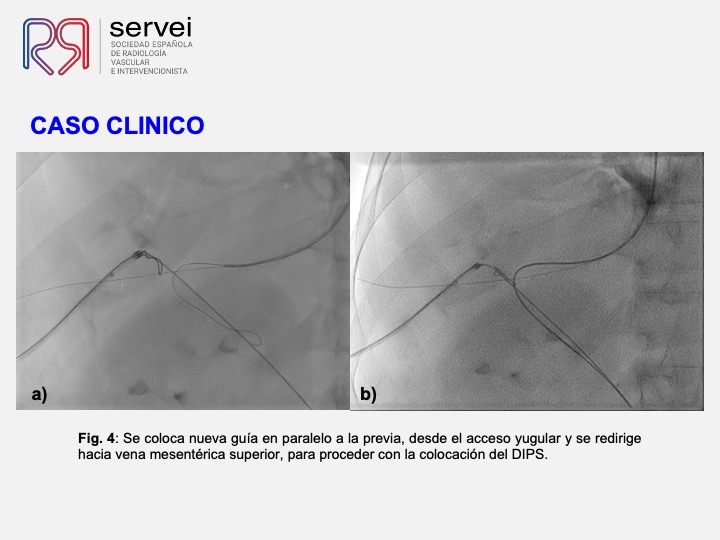

DIPS con técnica de “gun-sight”. Paciente con Síndrome de Budd-Chiari y eventual trombosis protésica